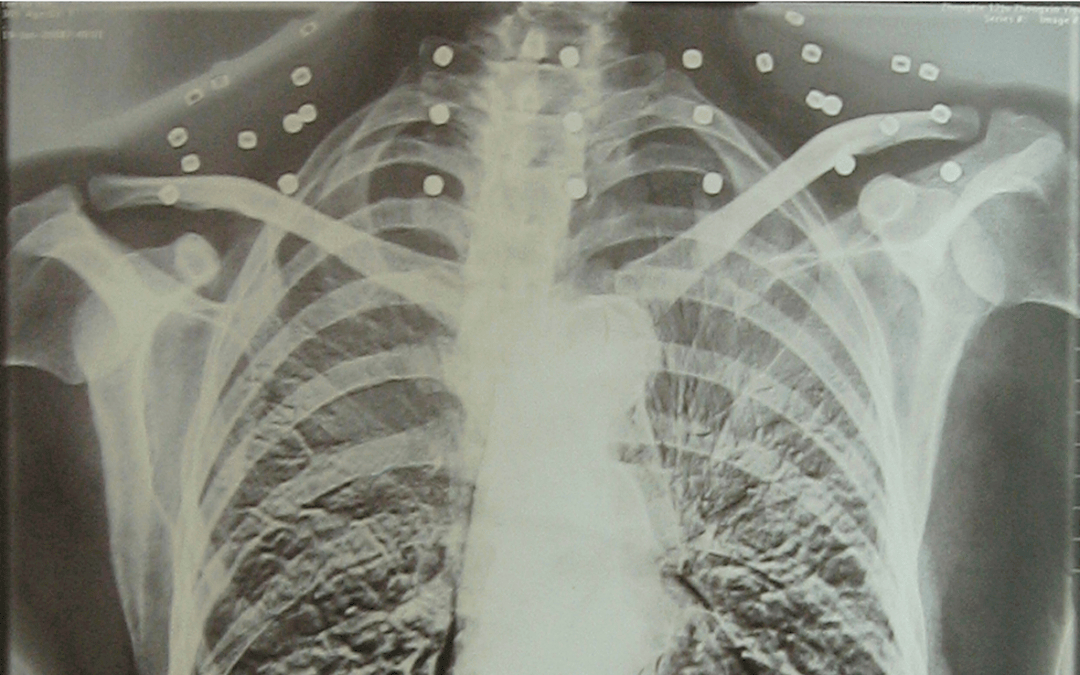

这张照片

是今年82岁的吴以先老人

拍摄的一张CT照

20年前

吴以先在一次做CT检查时

医生误以为他戴了项链

于是提醒要取下来再做检查

但实际上是

吴以先的颈部和腹部

共分布着33枚弹片

但是打进身体里的弹片

一直留在了体内

他体内的弹片都没有取出

身体留有弹片的位置就有痛感

但吴以先不考虑取出弹片

在他看来

这是他与战友并肩作战的见证

是他的勋章

与吴以先身上那33枚弹片